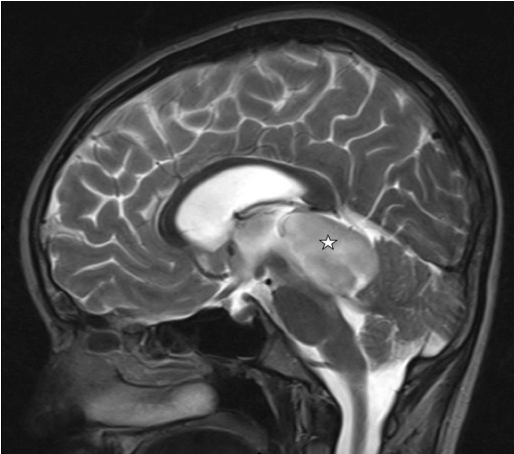

脊髓是一種少見的實(shí)體,是在兒科患者,暴露的癥狀大多是進(jìn)展性感覺運(yùn)動(dòng)和自主神經(jīng)功能缺損,繼發(fā)于脊髓內(nèi)多束受累...

原發(fā)性脊髓星形細(xì)胞瘤治療金標(biāo)準(zhǔn)是手術(shù)切除。二線治療包括放化療,輔助治療的較好方案尚未明確,巴特朗菲教授2021年2月將來華,國內(nèi)患者可預(yù)約咨詢其前沿治療方案...

神經(jīng)節(jié)膠質(zhì)瘤 是一種中樞神經(jīng)系統(tǒng)的腫瘤,懷疑起源于錯(cuò)構(gòu)瘤性神經(jīng)膠質(zhì)神經(jīng)病變的常見前體細(xì)胞。組織病理學(xué)上,這些腫瘤由神經(jīng)節(jié)細(xì)胞和膠質(zhì)細(xì)胞組成。它們在全部小兒中樞神經(jīng)系...

原發(fā)性顱內(nèi)間變性神經(jīng)節(jié)膠質(zhì)瘤在小兒患者中是少見的腫瘤。他們中的大多數(shù)表現(xiàn)為血壓升高或癥狀性癲癇,巴特朗菲教授2021年2月將來華為國內(nèi)患者解答病情...

英文摘要:Primary intracranial anaplastic gangliogliomas are rare tumors in the pediatric patient group.Most of them present with symptoms of elevated pressure or symptomatic epilepsy.Extraaxial location is far more common than axial loc...

毛細(xì)胞星形細(xì)胞瘤是一種低級(jí)別的中樞神經(jīng)系統(tǒng)腫瘤,硬膜內(nèi)髓外毛細(xì)胞星形細(xì)胞瘤獨(dú)自于原發(fā)實(shí)質(zhì)內(nèi)腫瘤的成人患者,因此相對(duì)很少被報(bào)道...